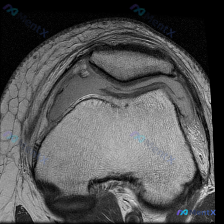

这是一份膝关节MRI检查的T1加权轴位(横断面)图像,扫描层面位于髌股关节水平,先整理一下基础读片结果:

- 解剖结构确认:前方为髌骨,后方为股骨滑车部,两侧可见髌骨内外侧支持带、股内侧肌/股外侧肌附着,髌股关节间隙清晰

- 骨质评估:髌骨及股骨滑车骨皮质连续光滑,未见骨质缺损或骨折;骨髓腔信号正常,均匀高信号脂肪影,无异常低信号排除骨髓水肿或肿瘤浸润

- 软骨评估:髌股关节软骨轮廓连续,未见局灶性全层缺损或软骨下骨暴露

- 软组织评估:关节间隙宽度正常,无明显病理性积液;滑膜无增厚,髌支持带结构连续;周围肌肉形态信号正常

- 局限性说明:该层面不包含半月板、交叉韧带,无法评估这些结构

读片初步结论:基于当前这张T1加权轴位图像,未见明确骨质病变、软骨缺损或软组织异常。